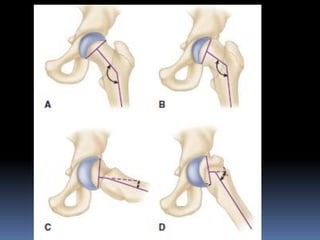

 OSTEOTOMY-

Two basic types:

close wedge osteotomy: usually near the physis to correct the deformity.

compensatory osteotomy: through the trochanteric region to produce

A)Through neck

near epiphysis.

B)Through base of

neck.

C)Through

intertrochanteric

region.